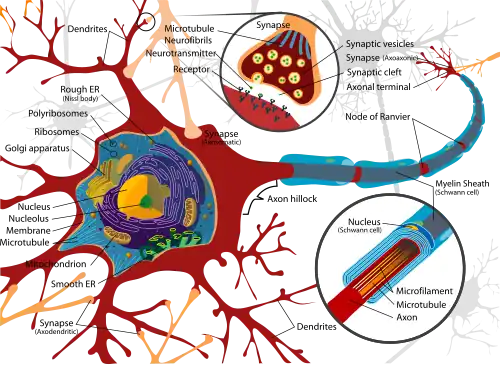

Selected image –

General images –

- Cell biology